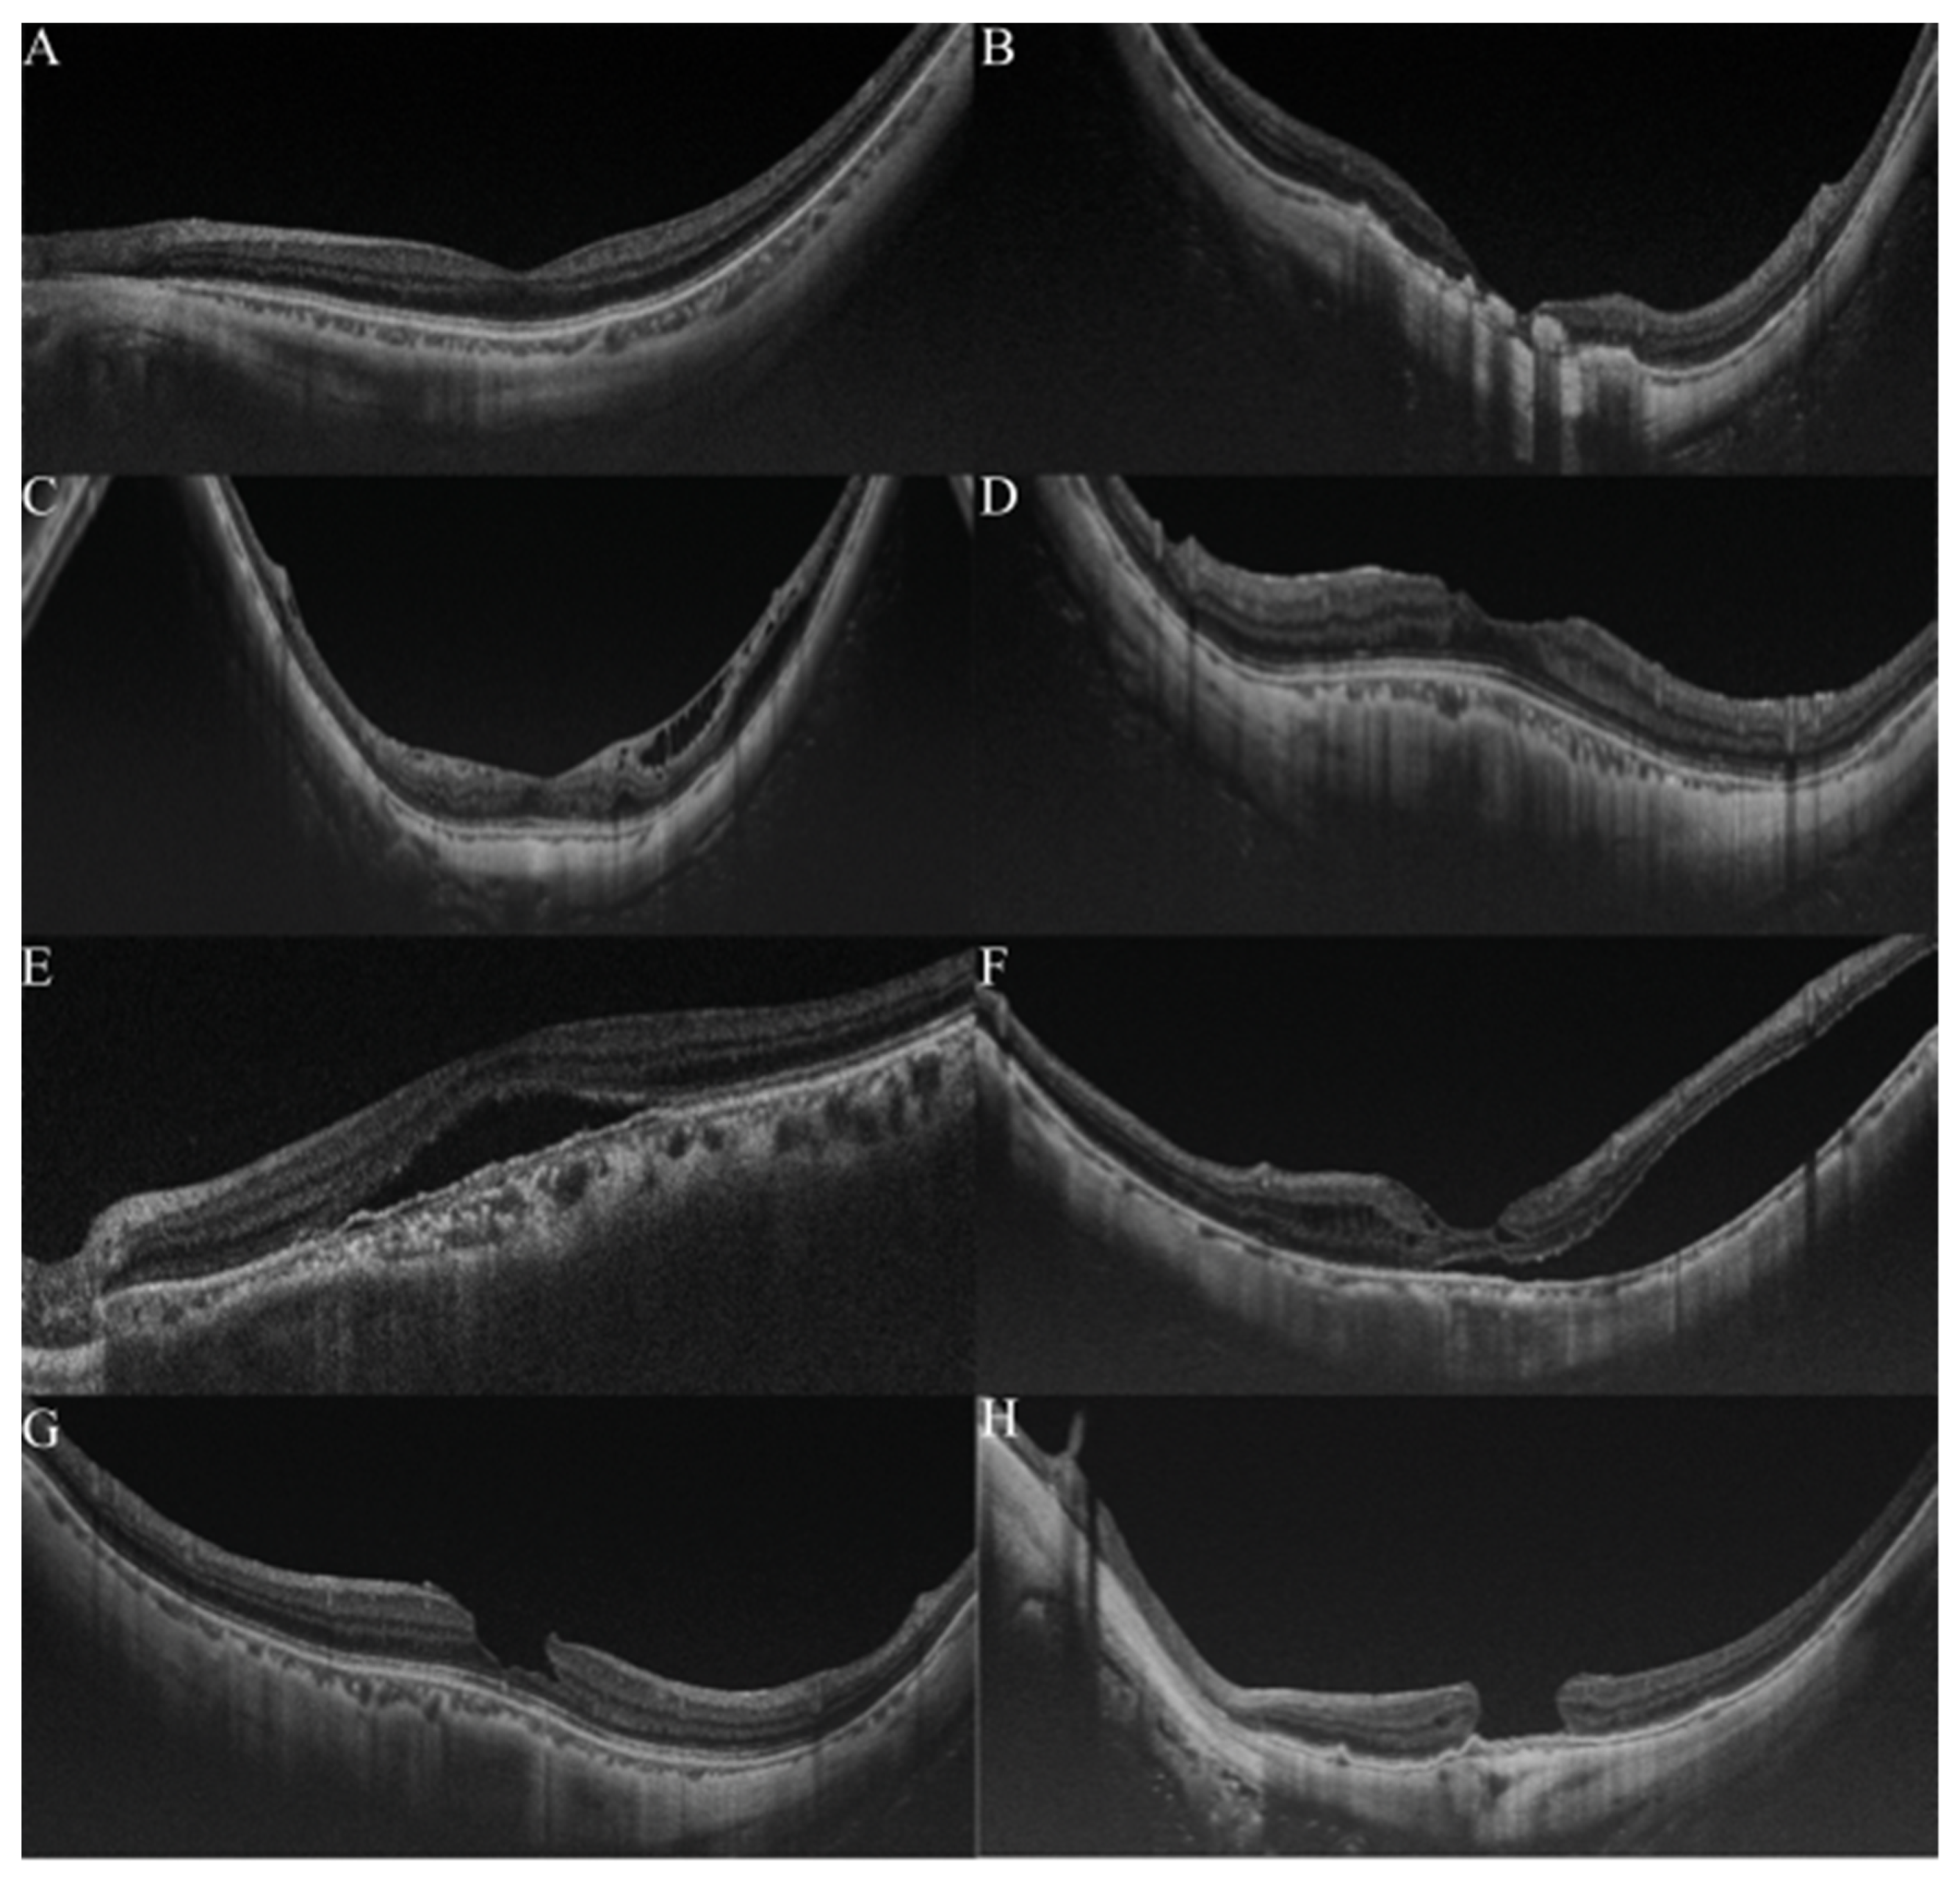

OCT is widely used for detecting and analyzing retinochoroidal disorders, and it has become the general method of examination used to assess the retina of myopic patients. Typically, in pathologic myopia, OCT images were always used to observe the pathological retinochoroidal changes or progression of retina degeneration (Figure 3). The OCT images were mainly used to examine myopic traction maculopathy (MTM), which is a spectrum of foveal tractional changes in highly myopic eyes [61]. All MTM-related alterations, such as retinoschisis, retinal detachment, and macular holes, can be identified in OCT images. Thus, it is expected that AI could assist physicians in grading pathologic myopia retinochoroidal changes in OCT images.

Figure 3.

Grading samples of myopic maculopathy in ocular coherence tomographic (OCT) images. (A). Myopic eye without myopic maculopathy. Each of retinochoroidal layer is clearly seen. (B). Myopic neovascularization (MNV). Hyperreflective materials can be seen above the retina pigment epithelium (RPE), and this component is attenuated in the tissue coherence signals below. (C). Retinoschisis. The splitting of the inner retina from the outer retinal layers with multiple perpendicularly aligned columnar structures connecting the split retinal layers. (D). Dome-shaped macular (DSM). An inward bulging of the retina pigment epithelium above the baseline connecting the RPE lines on both sides away from the DSM. (E,F). Retinal detachment. The neurosensory retina is detached from the RPE. (G,H) Macular hole. A tear above the RPE layer and an anvil-shaped deformity of the cracked edges of the retina. Reprinted from Validation of Soft Labels in Developing Deep Learning Algorithms for Detecting Lesions of Myopic Maculopathy from Optical Coherence Tomographic Images, Copyright (2021), with permission from Wolters Kluwer Health.